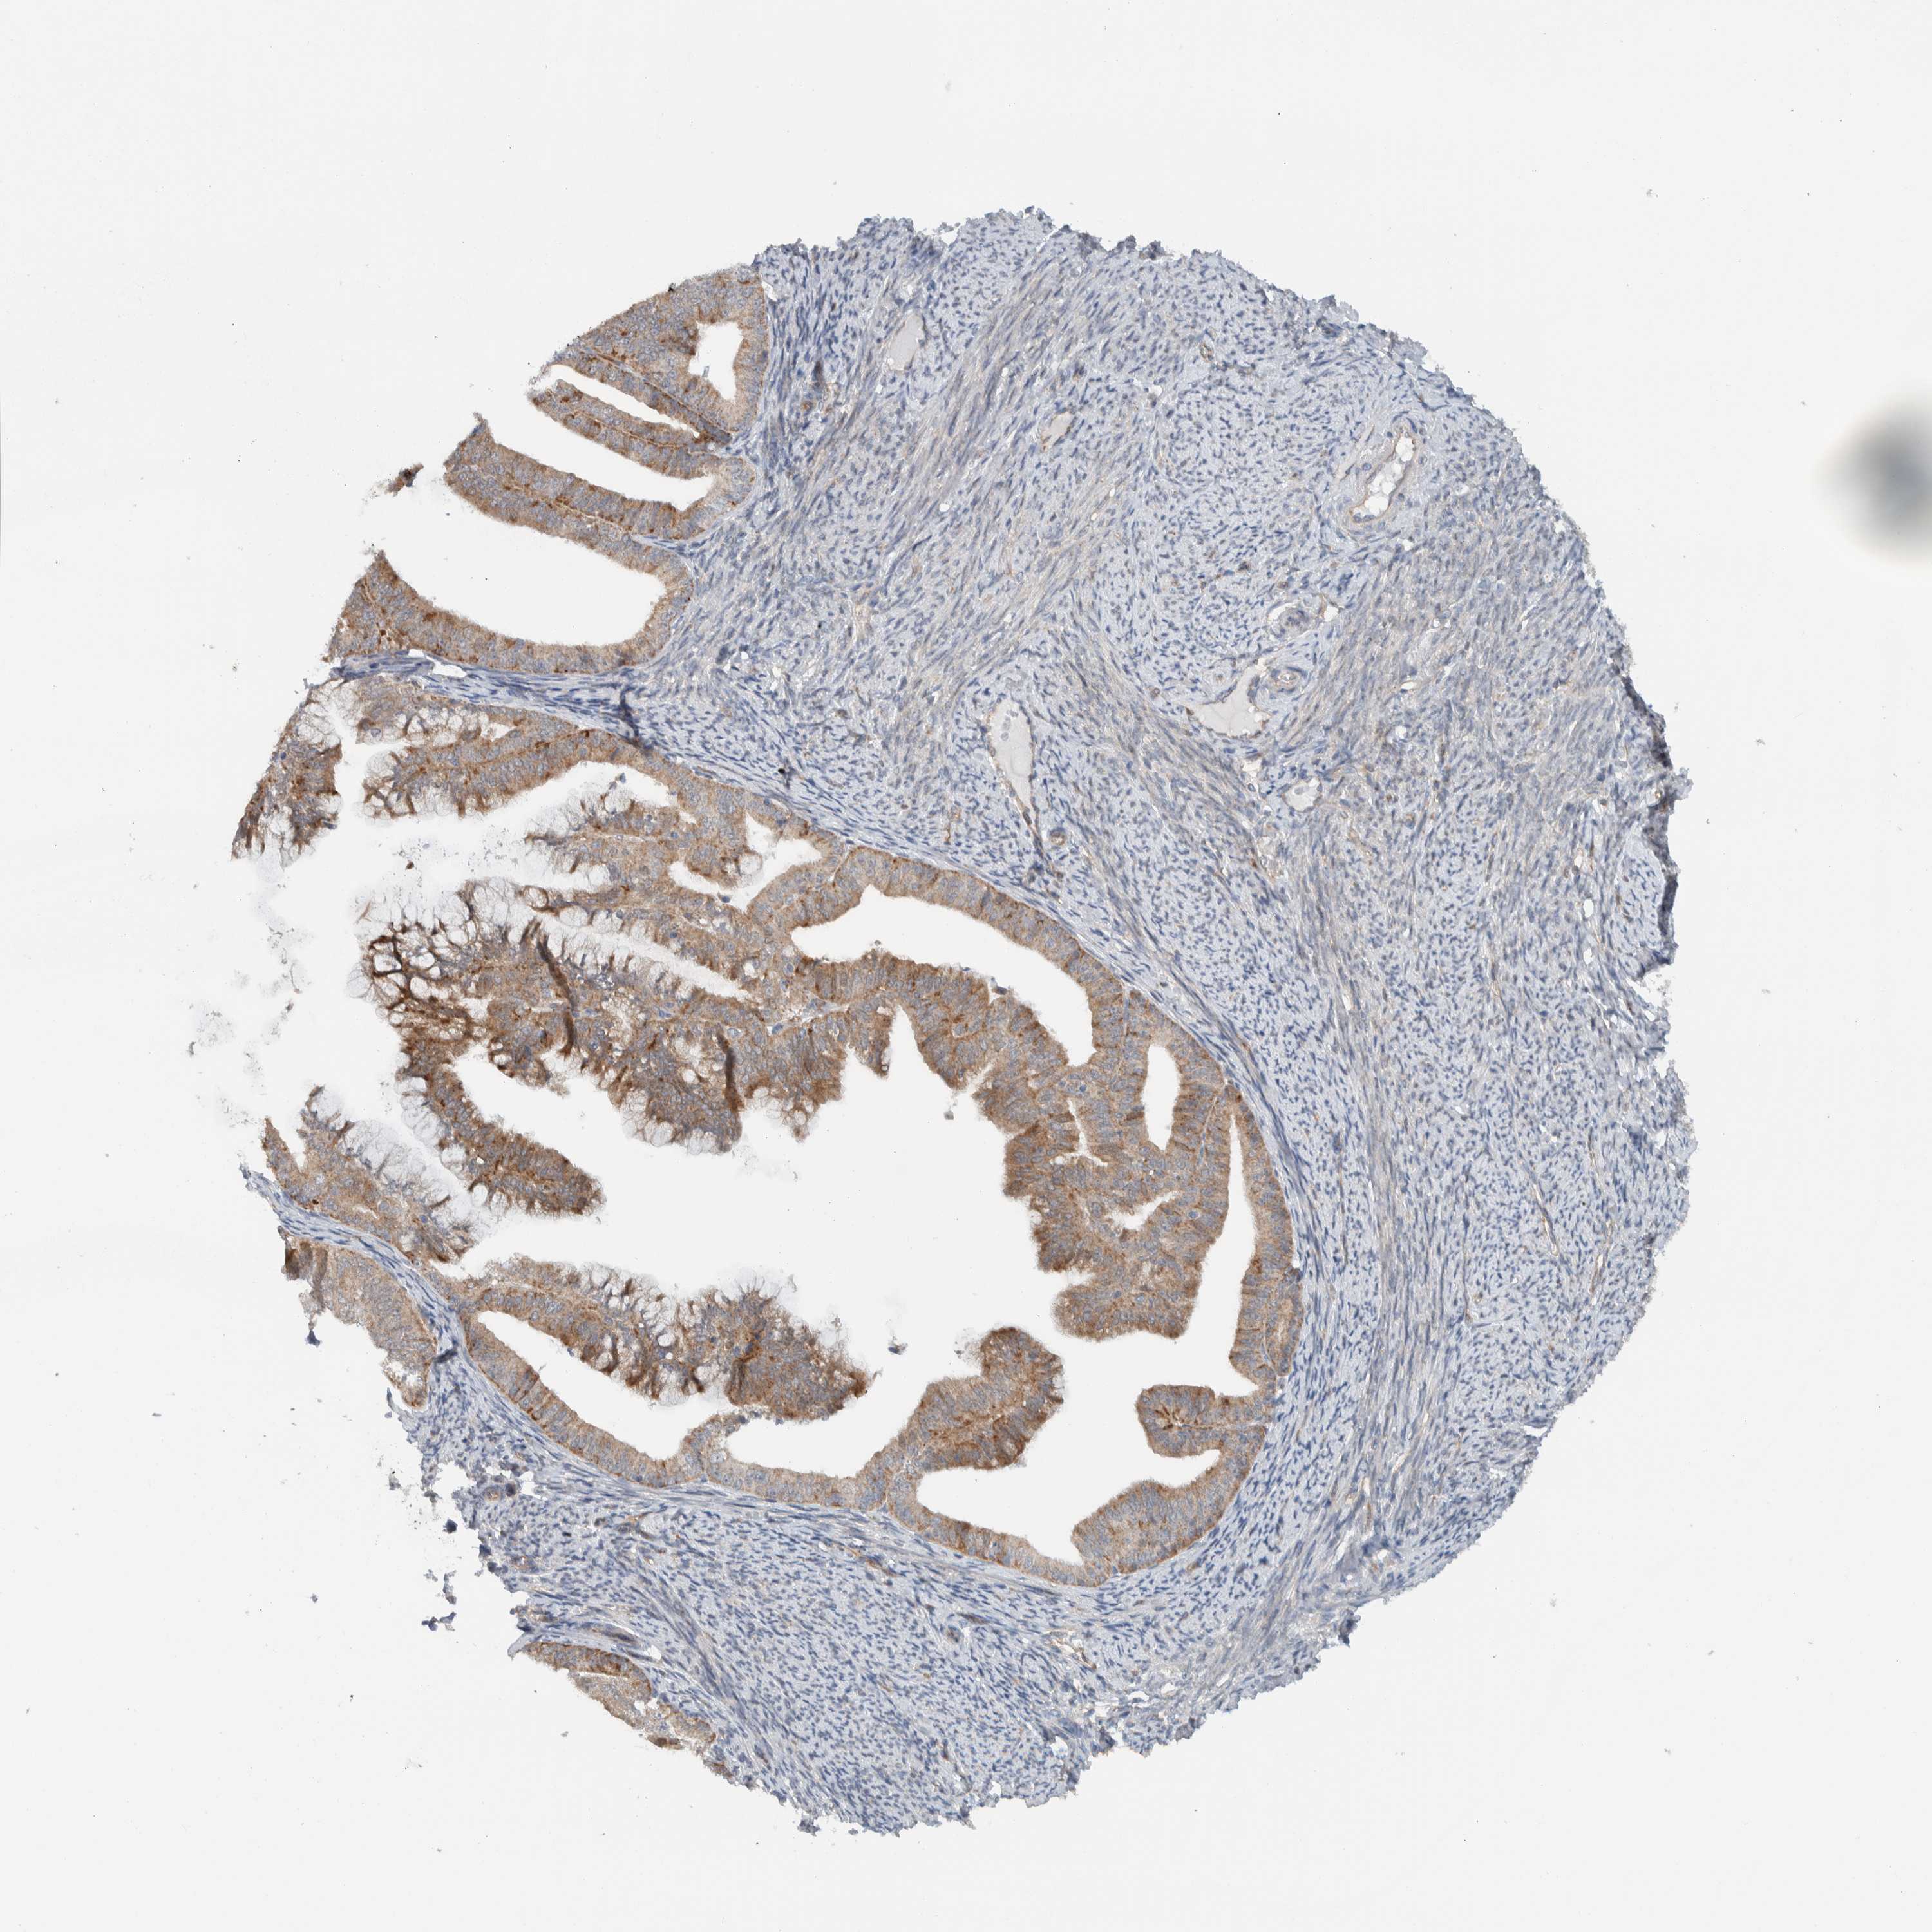

ENDOMETRIAL CANCER - Protein expressioni

A mouse-over function shows sample information and annotation data. Click on an image to view it in a full screen mode. Samples can be filtered based on level of antibody staining by selecting one or several of the following categories: high, medium, low and not detected. The assay and annotation is described here.

Note that samples used for immunohistochemistry by the Human Protein Atlas do not correspond to samples in the TCGA dataset.

Antibody stainingi

Antibody staining in the annotated cell types in the current human tissue is reported as not detected, low, medium, or high, based on conventional immunohistochemistry profiling in selected tissues. This score is based on the combination of the staining intensity and fraction of stained cells.

Each image is clickable and will lead to virtual microscopy that enables deeper exploration of all samples and also displays staining intensity scores, fraction scores and subcellular localization as well as patient and tissue information for each sample.

Antibody HPA024093

Staining

High

Medium

Low

Not detected

Intensity

Strong

Moderate

Weak

Negative

Quantity

>75%

75%-25%

<25%

None

Location

Nuclear

Cytoplasmic/membranous

Cytoplasmic/membranous,nuclear

Adenocarcinoma, NOS